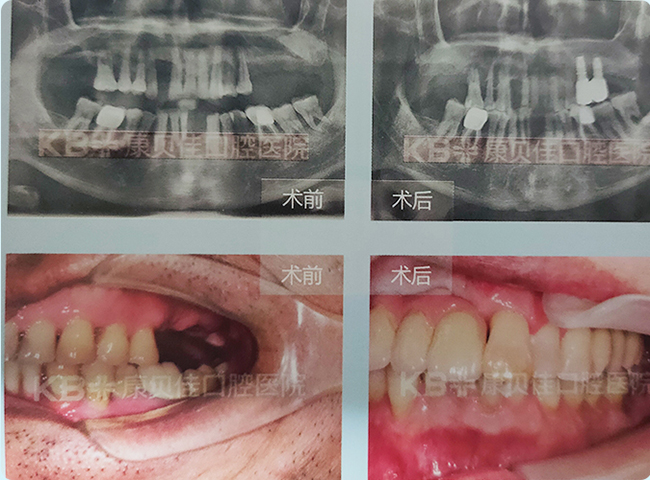

史先生 63岁

牙周病致牙齿松动脱落。种植即刻修复,种植术后6个月永久性修复。

治疗方案:

下颌种植4颗修复半口